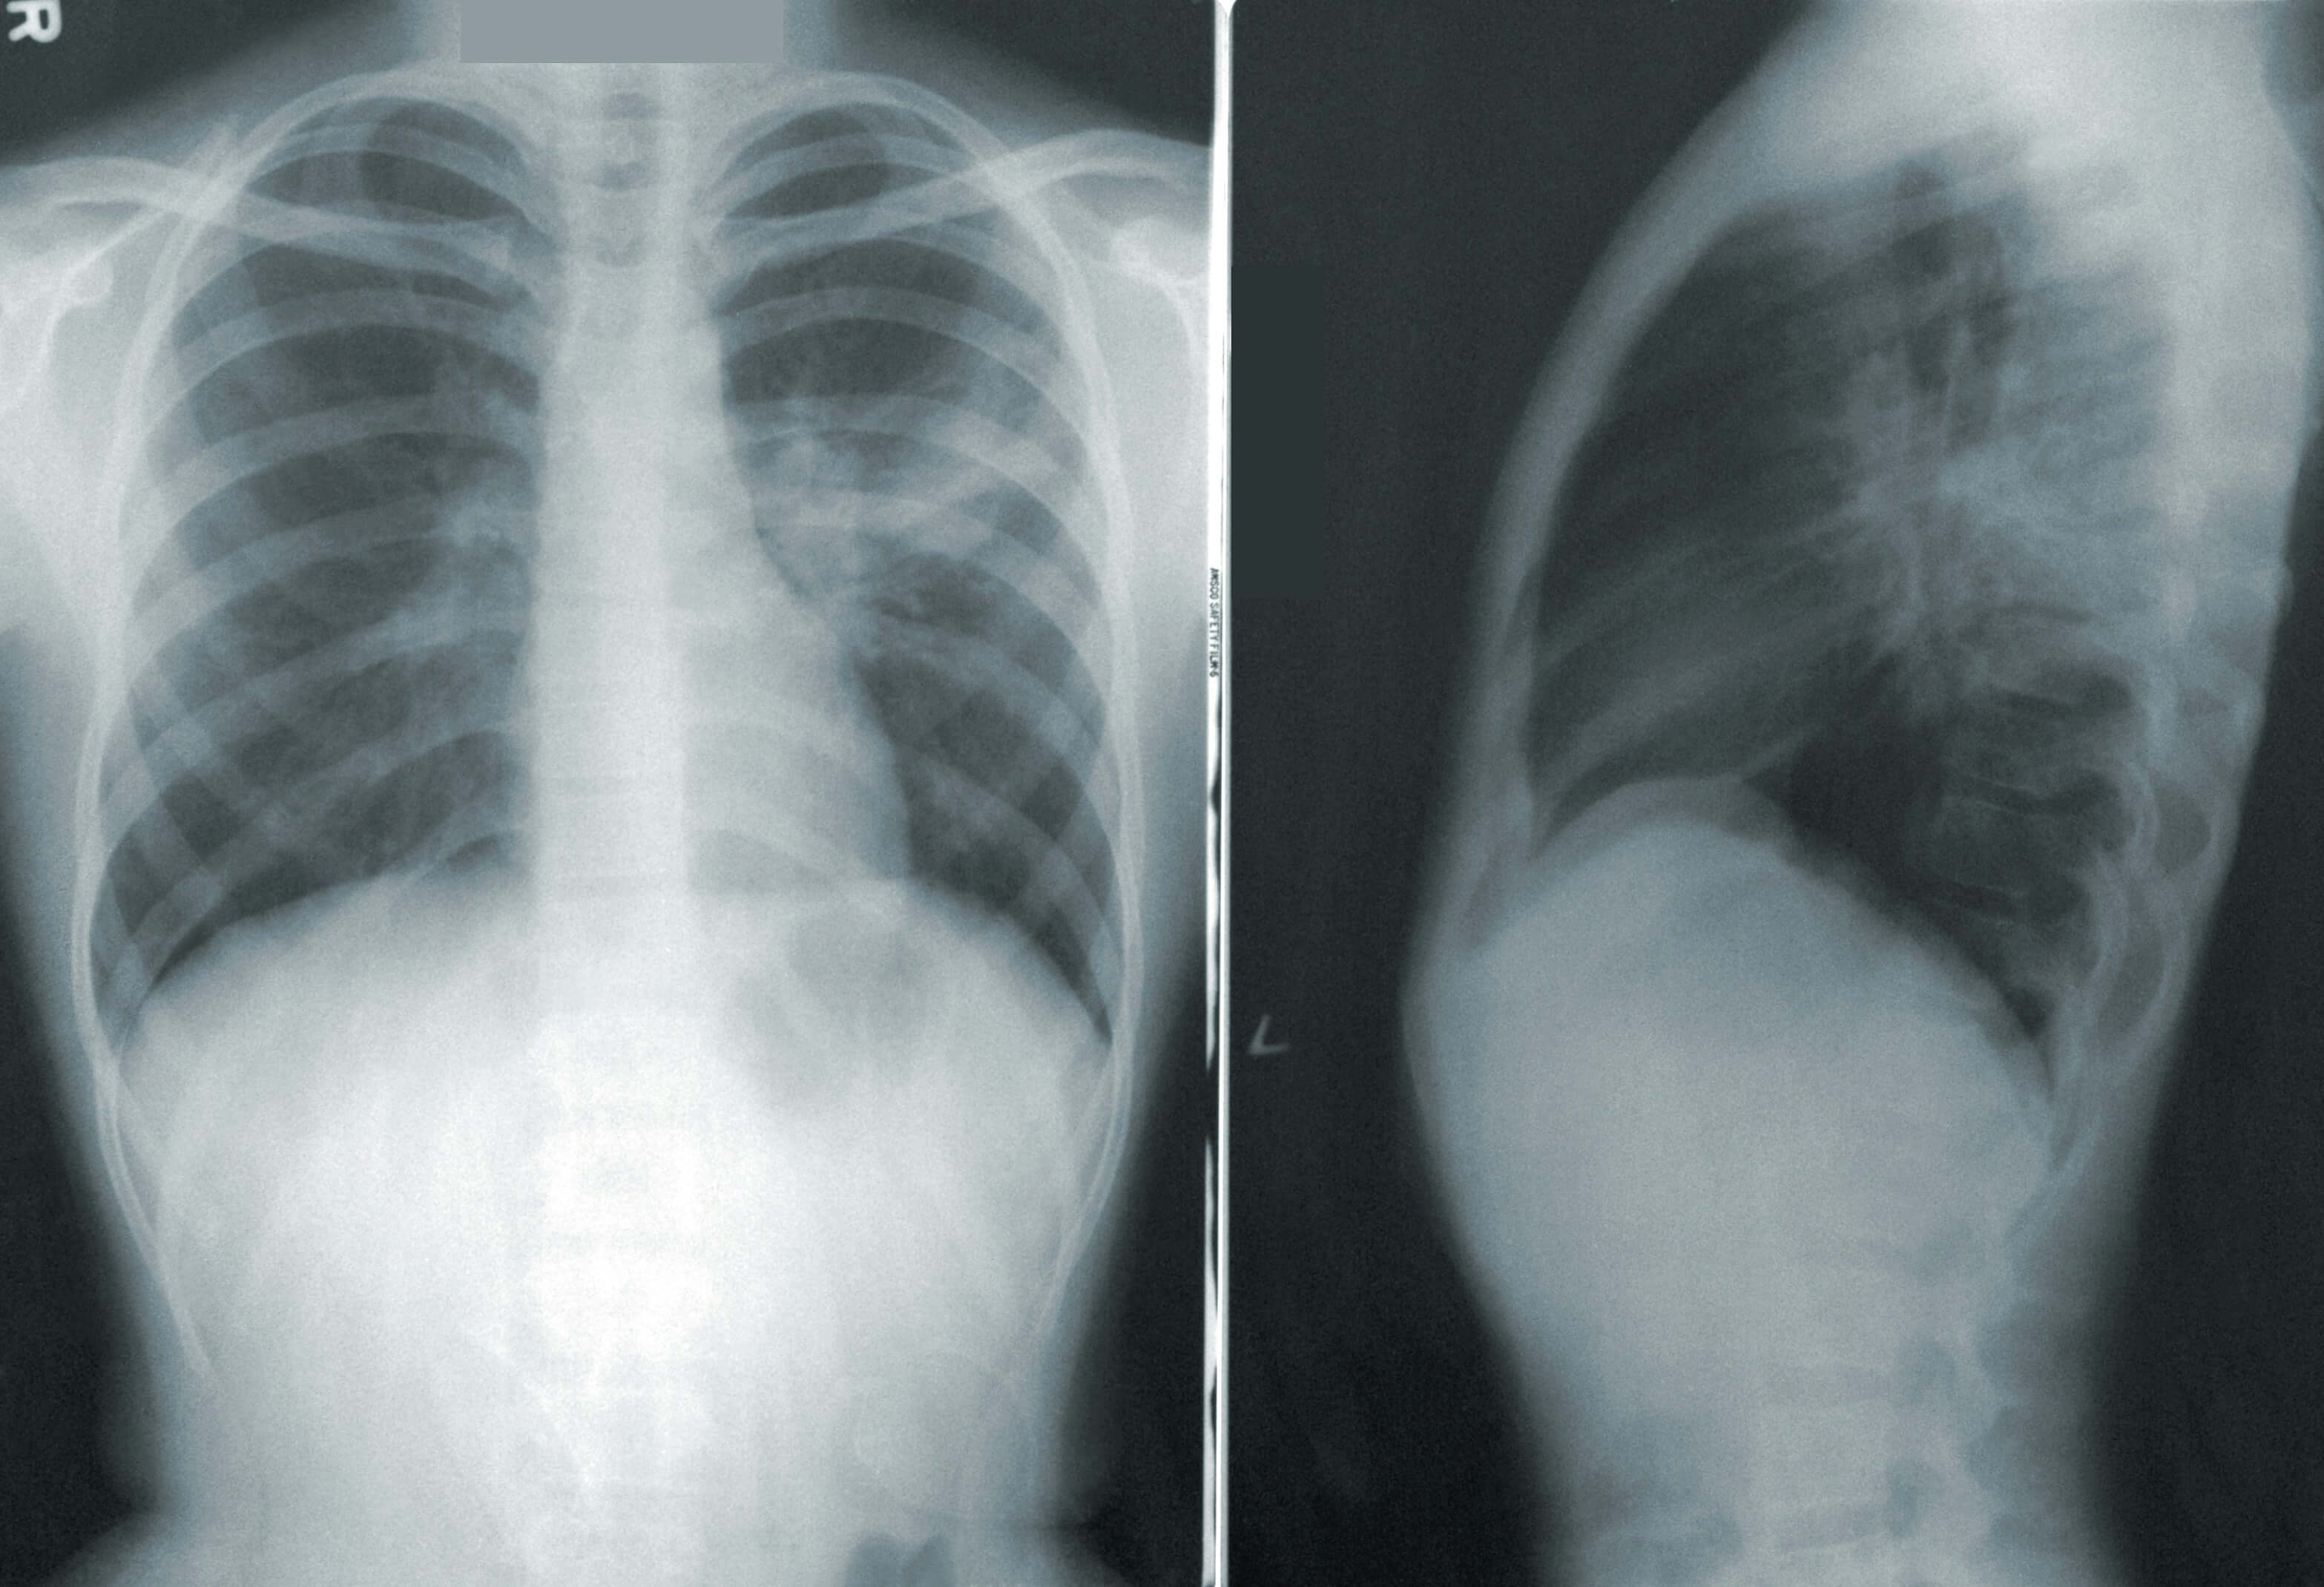

현대 사회에서 폐암은 조기 발견이 매우 어려운 질환으로 알려져 있습니다.

초기에는 특별한 증상이 거의 나타나지 않아 대부분 병이 상당히 진행된 후에야 이상을 느끼고 병원을 찾게 됩니다.

폐암은 초기에 발견될 경우 5년 생존율이 50% 이상으로 높아지지만, 진행된 상태에서 발견되면 생존율이 크게 떨어집니다.

폐암은 초기에는 특별한 증상이 나타나지 않는 경우가 많지만, 몸에서 보내는 미세한 신호들이 있습니다.